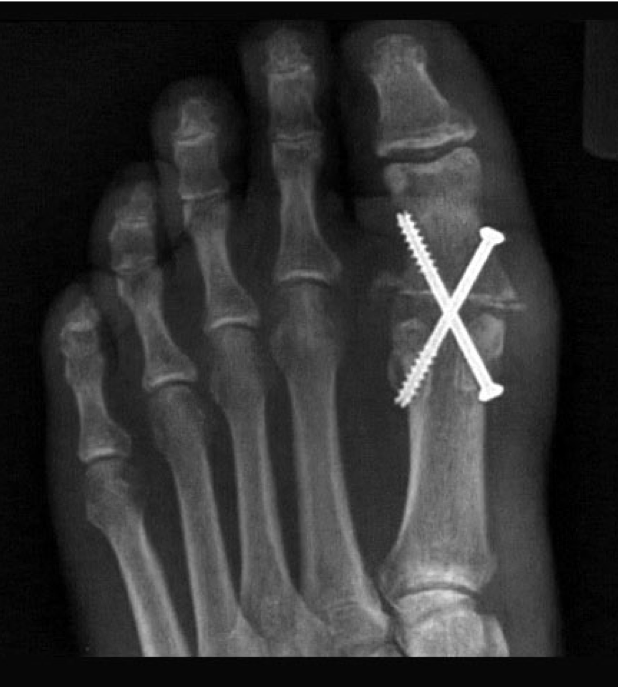

Hallux Valgus – Scarf osteotomy

Bone broken and shifted in the coronal plane

Hallux Valgus – basal osteotomy